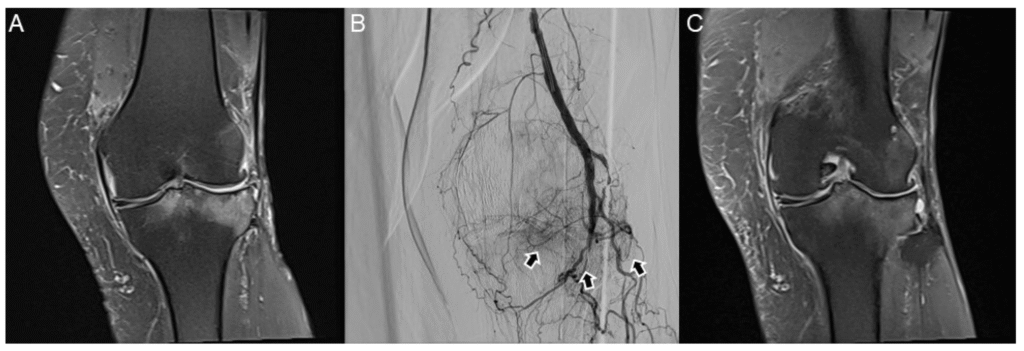

What causes Knee Pain in Osteoarthritis?

Knee osteoarthritis is caused by the gradual breakdown of cartilage — the smooth, slippery tissue that cushions your knee joint. As the cartilage wears away, the bones of your knee begin to rub against each other, triggering pain, stiffness, and inflammation.